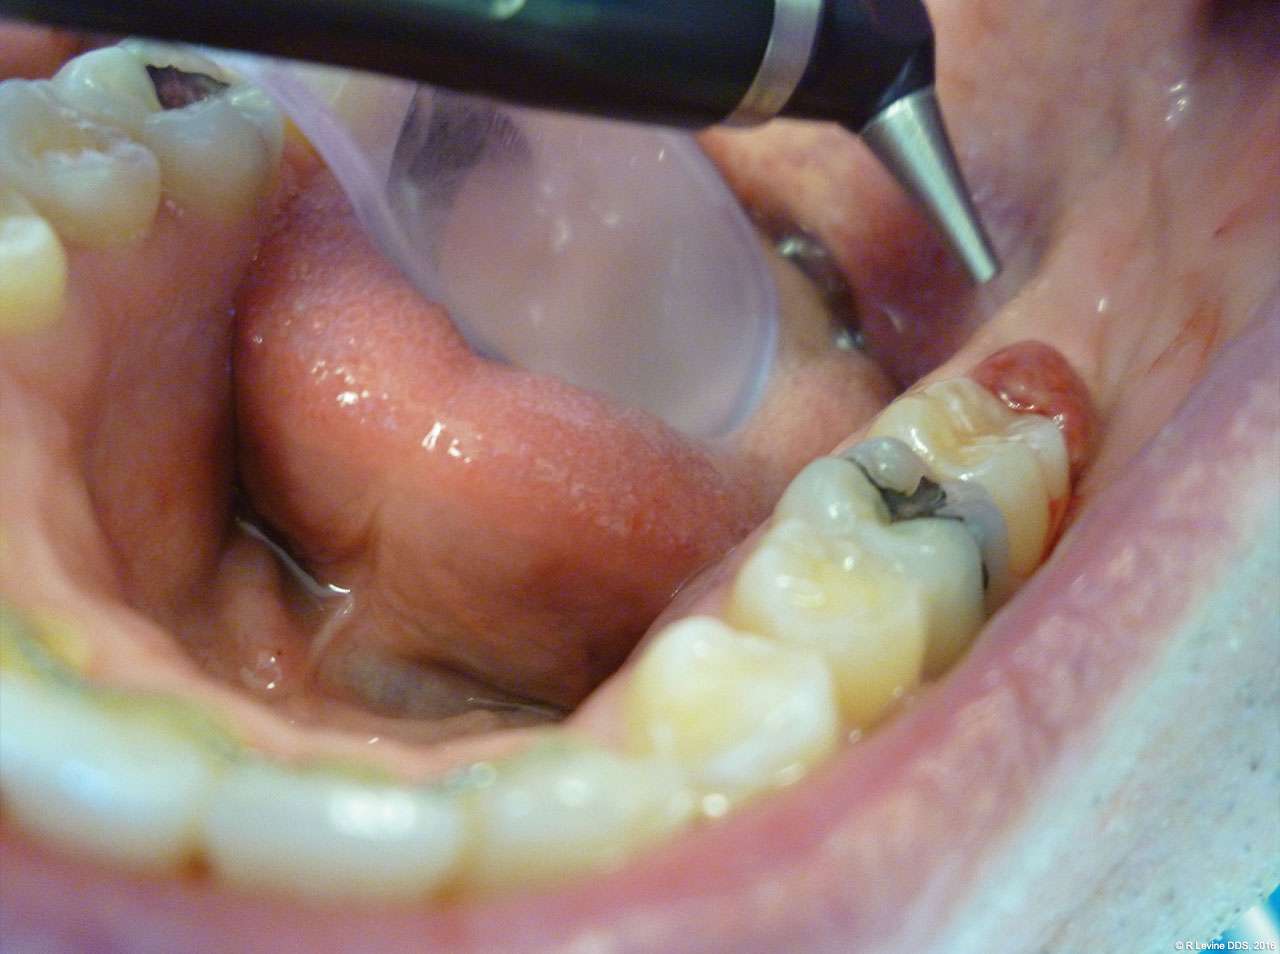

- After the initial pass with the laser, the inflamed gingiva bled slightly and the surgeon defocused the beam by increasing the nozzle-to-tissue distance to quickly obtain hemostasis (Figure 6). Note the excellent visualization and the clear operatory field.

- Additional tissue around the primary surgical site was superficially ablated to “feather out” the wound and make the treated area blend with the healthy gingiva better (Figure 7).

- Finally, the laser was defocused by moving the handpiece farther away from the surgical area and additional hemostasis was created. No suturing or dressing was needed and the wound was left to heal by secondary intention.